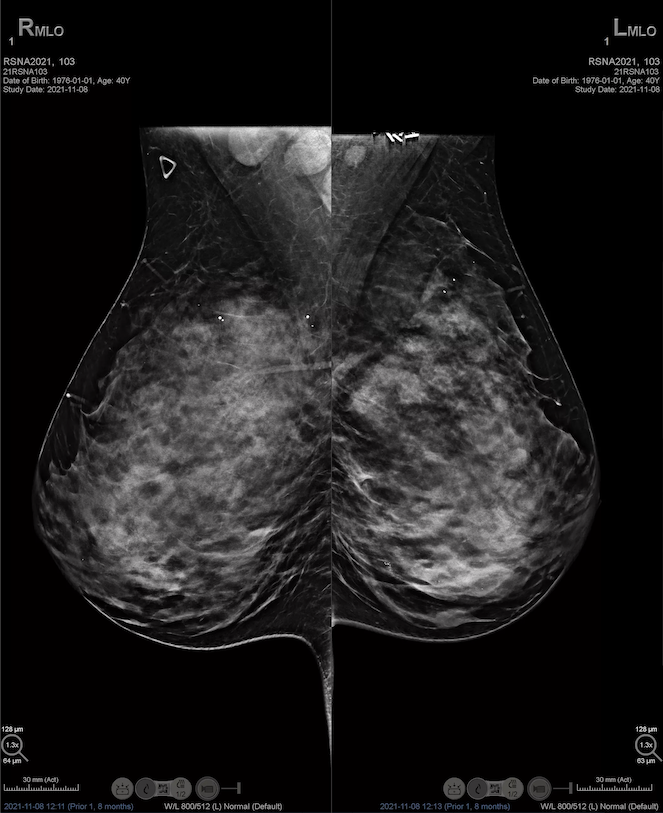

Hologic Selenia® Dimensions, tek bir tarama işleminde hem 2D dijital mamografi hem de gelişmiş 3D tomosentez teknolojisini bir arada sunar. Bu yenilikçi yaklaşım, radyologların meme dokusunun detaylarını daha eksiksiz değerlendirmesine olanak tanır ve teşhis doğruluğunu artırır. C-View™ sentezlenmiş 2D görüntü teknolojisi sayesinde, radyasyon dozu analog mamografi seviyelerine çekilirken, görüntü kalitesinden ödün verilmez. Bu özellik, özellikle yoğun meme dokusuna sahip hastalarda yüksek tanı güvenilirliği sağlar ve erken kanser tespitinde kritik rol oynar.

Hologic Selenia® Dimensions, yoğun meme dokusuna sahip kadınlarda bile yüksek çözünürlükte ve detaylı görüntüler sunar. Bu teknoloji, meme dokusunun yoğunluğundan kaynaklanan tanı zorluklarını aşarak, gizli kalabilecek küçük lezyonların tespit edilmesini mümkün kılar. Klinik çalışmalar, bu sistemin yoğun meme dokusunda meme kanseri tespit oranını anlamlı ölçüde artırdığını ve erken teşhiste önemli rol oynadığını göstermektedir. Böylece risk altındaki hastalar için güvenilir ve etkili bir tarama çözümü sağlar.

Klinik Güvenilirlik & Hologic Etkinliği

Hologic’in ileri teknolojilere dayanan sistemleri, klinik çalışmalarda güvenilirlik ve etkinlik açısından güçlü kanıtlar sunmaktadır. Büyük ölçekli bir retrospektif çalışmada (2013‑2023 arasında 184.006 tarama incelenmiştir), yüksek çözünürlüklü (High-Resolution, HR) tomosentez, standart çözünürlüklü taramaya kıyasla 1.000 kadın başına kanser tespit oranını 4.87’den 5.38’e çıkarmıştır. Bu artış, erken teşhis potansiyelini ciddi şekilde artırmaktadır.

Öte yandan, Hologic Clarity HD ile birlikte kullanılan Intelligent 2D ve diğer teknolojilerin klinik pratikte yalancı pozitif çağrı oranlarını düşürdüğü, görüntü netliğini artırdığı ve okuma sürelerini kısalttığı yönünde radyologlar tarafından olumlu geri bildirimler alınmıştır. Bu veriler, Hologic çözümlerinin tanı doğruluğu ile verimliliği dengeleyen ve güven veren bir altyapı sağladığını göstermektedir.